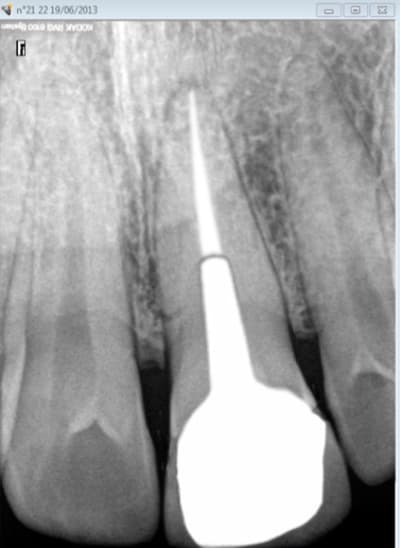

cyber_quenottes

01/03/2016 à 10h50

votre avis sur ce travail ?

je précise ZERO mobilité

Bribridge uhapmu - Eugenol

La nature est bonne fille et l'obturation est un élément parmi d'autres qui concours au succès ou non du traitement sur le long cour.

Tu fait traiter le cas par un ordinateur avec un logiciel de reconnaissance d’image ou par un "expert mutuelle" pour générer des indus, ca ne passe pas. Il manque une expertise sérieuse avec un avis clinique.

Après en fonction de l’évolution de la santé du patient et des traitements, tu peux avoir à un moment ou un autre une évolution défavorable. A voir aussi avec la qualité de la pâte d'obturation.